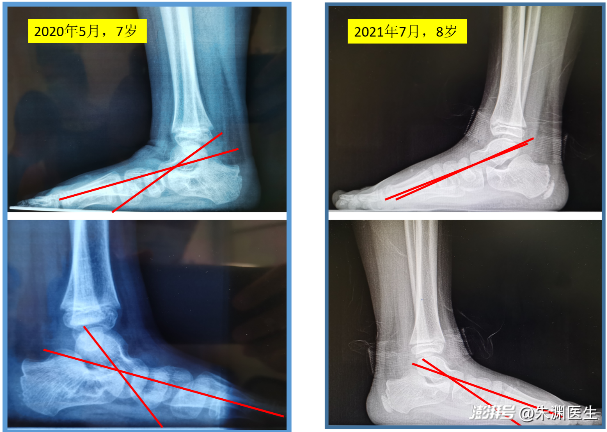

矫形鞋垫结合运动康复治疗儿童平足症。治疗1年后足弓有明显改善。